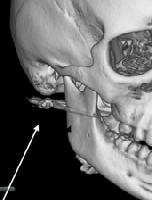

В случае перелома шейки бедра компания МосРентген Центр госпитализирует в Склиф для эндопротезирования.